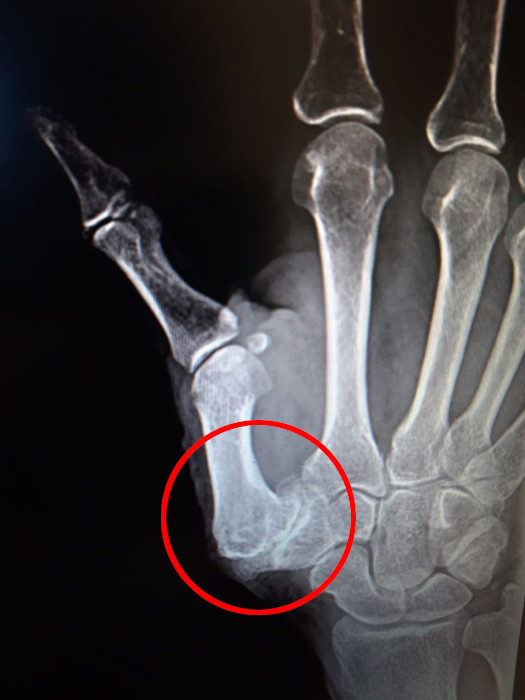

Rizoartrosi

- Descrizione: Artrosi dell'Articolazione carpo-metacarpale della Mano. Presenta degenerazione della Cartilagine articolare con compromissione del movimento e Dolore sia al movimento che a riposo.